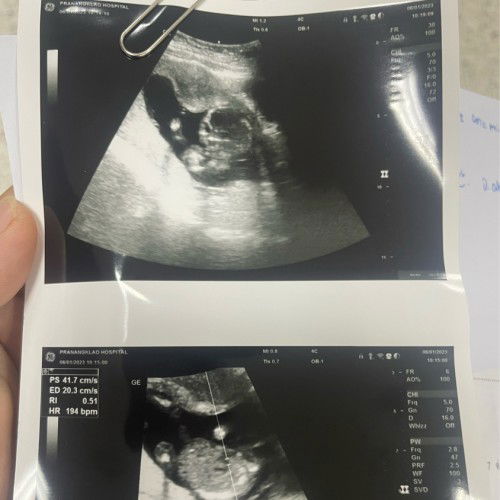

ใบอัลตราซาวด์

แม่ๆช่วยดูรูปด้านบนหน่อยค่ะคือน้องหันหน้ามาใช่ไหมคะ แม่ดูไม่เป็น แล้วหัวใจเต้น194คือผิดปกติไหมคะ หมอไม่ว่าอะไรเลยค่ะ#คุณแม่ๆช่วยแนะนำหน่อยค่ะ #ท้องแรกคะ